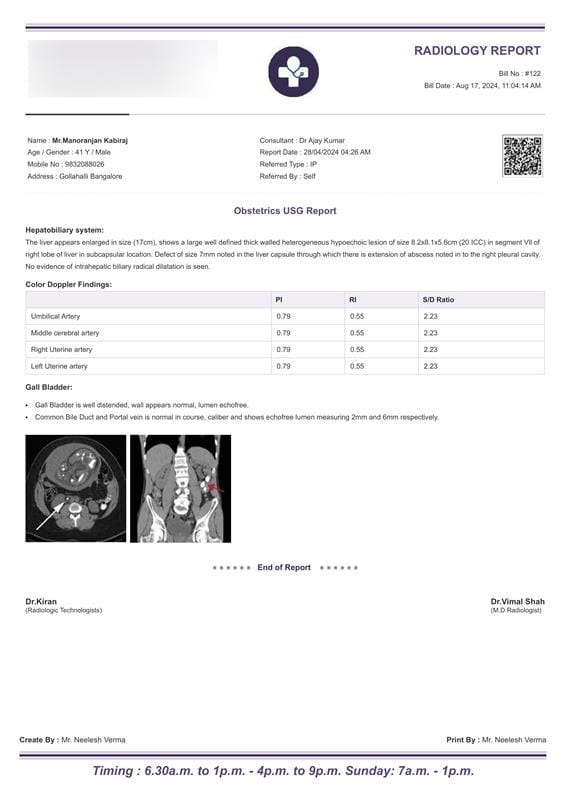

Example: The radiology report identifies the patient as “Mr. Manoranjan Kabiraj, a 41-year-old male from Gollahalli, Bangalore.”

Example: The report was prepared at “Elcura Healthcare, Solan, Himachal Pradesh,” and the radiologist is “Dr. Vimal Shah.”

Example: The report was issued on “28/04/2024 at 04:26 AM” with the bill number “#122.”

Example: The radiology report mentions “Obstetrics USG” and describes the findings in the hepatobiliary system, indicating “an enlarged liver with a heterogeneous lesion in segment VII of the right lobe.”

Example: The liver is described in detail, noting “a lesion of size 8.2×8.1×5.6 cm” and a “defect in the liver capsule extending into the right pleural cavity.”

Example: The report lists Color Doppler findings for the umbilical artery, middle cerebral artery, and uterine arteries with consistent measurements.

Example: The gall bladder is noted as “well-distended with a normal wall and echofree lumen.”

Example: The report is signed by “Dr. Vimal Shah, M.D. Radiologist.”

Example: The report was created and printed by “Mr. Neelesh Verma” with timing details mentioned for operational hours.